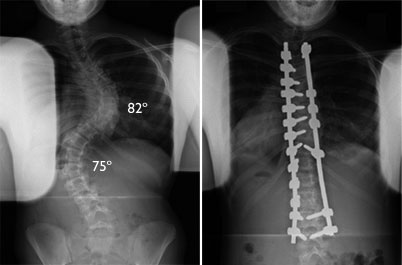

oui, pour les grosses déviations. Pour ma part j'avais une déviation de 70°, souvent c'est un double car le corps bizarrement en fait une autre de l'autre côté pour compenser. Ici une photo d'un cas plus grave que le mien encore.